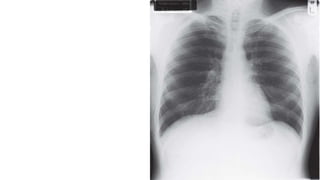

 The chest X-ray

 The computed tomography scan